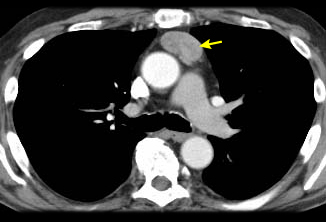

[Figure caption and citation for the preceding image starts]: Tomografia computadorizada (TC) do tórax mostrando timoma em estádio III de Masaoka-Koga com comprometimento da parede torácica anterior e invasão da região medial do pulmão esquerdoDo acervo de Cameron Wright, MD; usado com permissão [Citation ends].